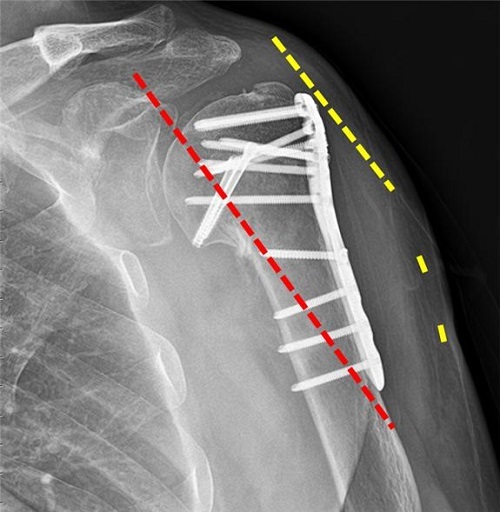

어깨뼈 골절 수술 후, 입원 중에는 주로 진통제가 투여되어 통증을 관리합니다. 이로써 입원 중에는 통증이 그리 심하지 않게 느껴질 수 있습니다. 상완골 골절의 경우 핀고정 수술이 주로 시행되며, 수술 후에는 상완골의 고정이 유지됩니다.